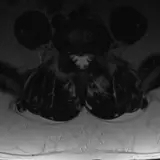

Over 2,100 interactive radiology cases, curated by radiologists for your level of training. Scroll, window, and view cases full screen — just like on PACS. Click linked findings in each writeup to jump straight to them on the image. Cases include sample reports, a focused discussion section, original illustrations, and videos.

Casos totalmente interactivos con las herramientas que esperaría de un PACS: scroll, ventana, zoom, pan, mediciones, ROI y modo de pantalla completa.

• Anotaciones enlazadas

Anotaciones extensas resaltan los hallazgos clave directamente sobre los casos. Haga clic en los hallazgos enlazados dentro de la descripción del caso para saltar a su ubicación exacta en el estudio.

Aprenda con eficiencia gracias a hallazgos de imagen anotados e ilustraciones